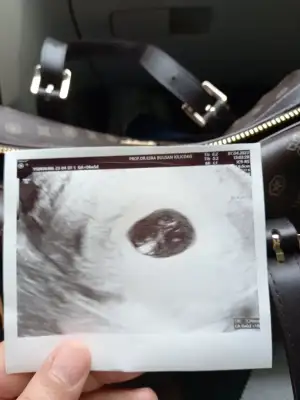

Vajinalvajinal ultrason ise kız ama karından ise erkek olduğunu anlıyorum :)

Hepsini anlamıştım burada kafam karıştı, bebek ortada olsa da sağa doğru duruyor. Plesantası da o tarafta değil mi? beni aydınlatır mısınKarından ise Ramzi teorisine göre erkek bariz

Ben hala anlayamadım kafam basmadi vajinal bakıldı sizce nedirŞunu şuraya koyayım kıslar kendiniz de anlayabilirsiniz 9. Haftadan sonra. Nub teorisinin ramziye göre tutma olasılığı daha fazla bildiğim kadarıyla

9 haftalık olan ultrasondan bahsediyorsun dimi? Canım ramzi teorisi 6-8 haftalık arasında bakılıyor dediğim gibi. Bebek büyüdükçe sol ya sağ kavramı değişiyor hareketlendiği için anlayamazsın. 9. Haftadan sonra da hareketleniyor zaten ramzi teorisini anlayamayız o yüzden nub daha sağlıklı oluyor o haftalarda .Hepsini anlamıştım burada kafam karıştı, bebek ortada olsa da sağa doğru duruyor. Plesantası da o tarafta değil mi? beni aydınlatır mısın

Seninki nub bakmak için erken zaten ramzi teorisine göre kız vajinal bakıldıysaBen hala anlayamadım kafam basmadi vajinal bakıldı sizce nedir